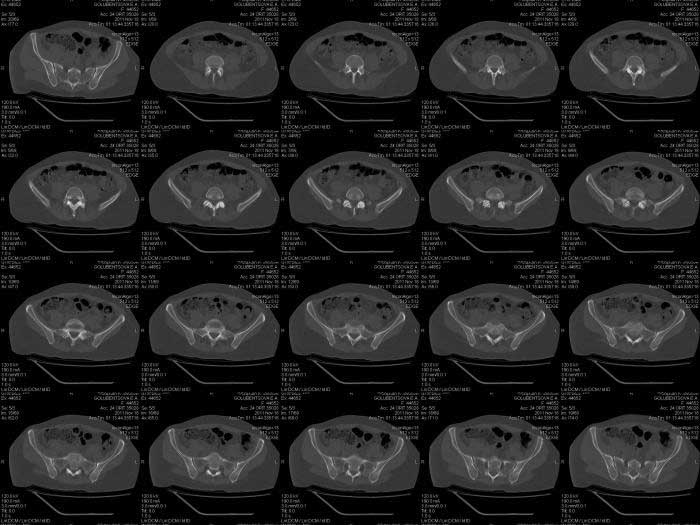

Кт снимки

КТ срезы помогают увидеть мелкие фрагменты и маргинальную импакцию, но на ваших мелких срезах трудно увидеть повреждение боковой массы крестца? Классифицировать перелом вертлужной впадины по Летурнелю все таки привычнее на косых Judet снимках.

Некоторые переломы вертлужной впадины между собой трудно отличаются, и надо проводить дифференциальную диагностику переломов: Т-образного, двух колонного и комбинации поперечного с переломом задней стенки (Associate

Transverse &Posterior Wall). Отсутствие вовлечения крыла подвздошной кости при двухколонном и наличие перелома в седалищной кости говорит о

Т-образном переломе.